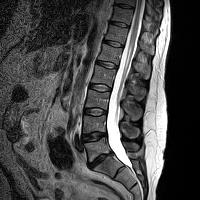

MRI Not Necessary for All Low Back Pain

MRI makes pretty pictures (and sometimes not so pretty when there are disc herniations, etc., that look bad but may not be cause of pain!), but they don’t diagnose. Physicians diagnose via clinical examination and observation and determine when and if an MRI is needed. (3) Aurora Chiropractic Center is most capable of diagnosing and managing back pain and its tests. The Cox Technic system of care looks for that 50% relief of pain within 30 days as a gauge of improvement and further testing.